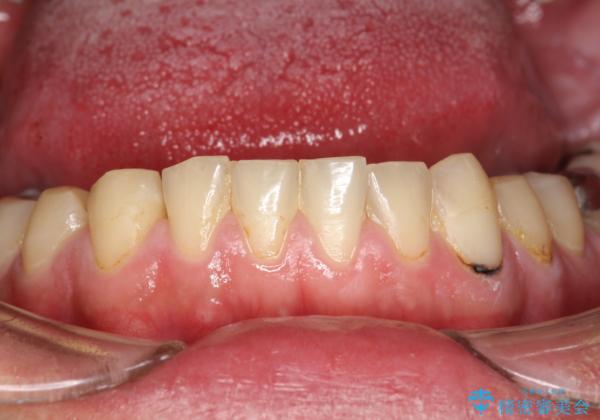

- なんとなく、口臭が気になりだしたためクリーニング希望で来院されました。PMTC30分コースを行いました。

虫歯や歯周病・口臭などの原因となるプラーク・歯垢(細菌の塊)は、べたべたと歯にくっつきやすく、また歯と同じような色をしているので見落としやすいものです。

虫歯や歯周病・口臭などの予防のためには、磨き残しやすい場所を染め出し液などで把握しておくことや正確な歯磨き方法を知ることがとても重要です。

綺麗に磨いたつもりでも、歯ブラシが当たりにくい所、苦手な所には、磨き残しがあるものです。

PMTCの際には、必要に応じて歯磨き指導も行います。

また、PMTCを行うことで、ステインやバイオフィルムが除去され、ご自身本来の歯の色となります。